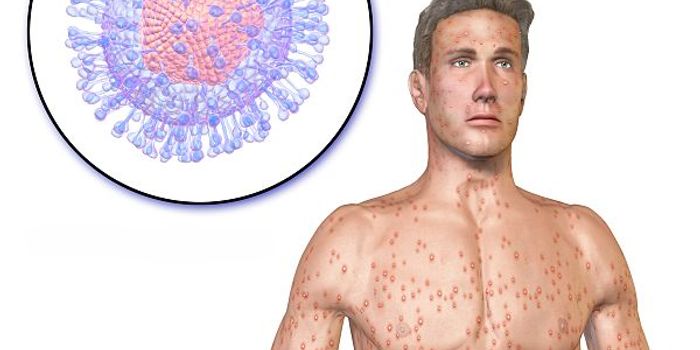

AUG 10, 2017

Immunology

In very rare cases - two in 10,000 people experts say - a chickenpox infection can trigger extremely dangerous brain inf